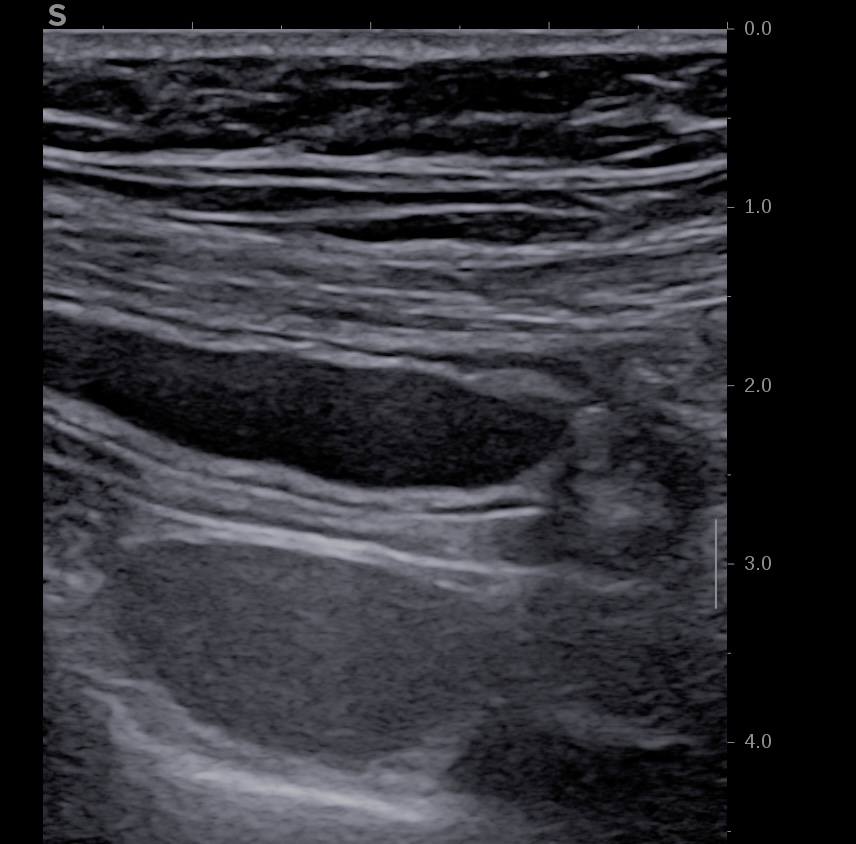

Image échographique de l'appendice au niveau du caecum

Corps de l'appendice vermiculaire distendu (8 mm de large)

Pointe de l'appendice distendue (7.5 mm de large)